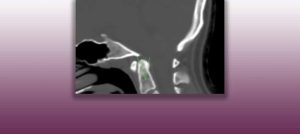

Institut Chiari & Siringomielia & Escoliosis de Barcelona is highly specialized neurosurgical center dedicated to the diagnosis and treatment of spinal and brain disorders, with a focus on the clinical concept of Filum Terminale Disease. Conditions treated include: